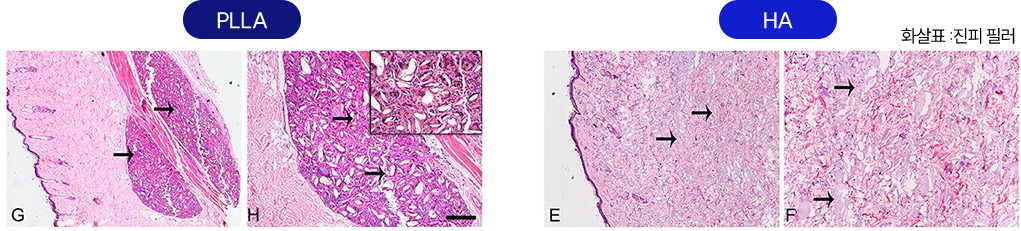

탄력 개선

탄력 개선